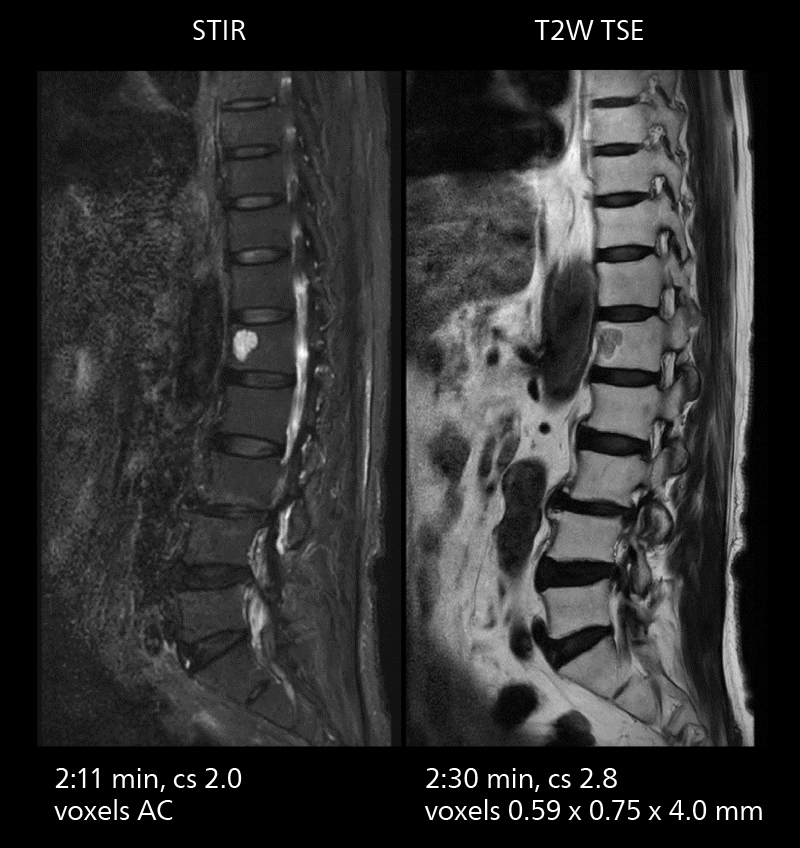

With SmartPath to Elition X the team can obtain excellent quality DWIBS imaging and reduce imaging time. Other sequences also fit in the examination slot. This case shows left paravertebral neurogenic tumor and Th10 vertebral hemangiomas.